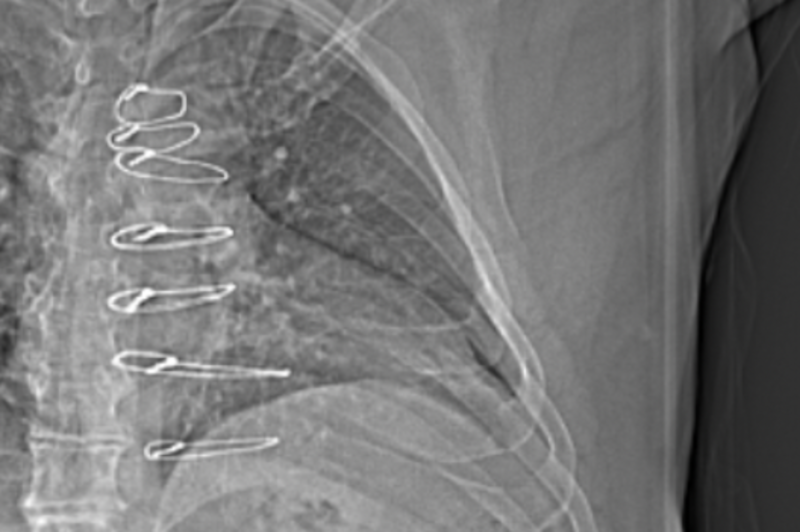

As my appointment with Dr. Abu-Omar proceeded, I learned that my assumption about the appointment was completely wrong. I learned that while it is very rare, chest pain like mine can sometimes be caused by the sternal wires that were left in my body after the surgery. (To the right I added for a second time the same X-ray photo from April 4, 2024, that clearly shows the median sternal wires, and a close-up photo taken from the June 6, 2024, CAT Scan.)

The appointment ended with a recommendation to have the sternal wires in my chest surgically removed (the wires are no longer needed, since my sternum had healed a year ago), and a promise to receive a call the next workday (Tuesday, September 3rd) with a scheduled surgery date. I was told that it was a simple, short operation (that they could slip me in between other operations). I most likely would go home the same day, but was told to be prepared to stay overnight, if needed. I was also advised that the incision from re-opening the scar area of my chest should heal in approximately two weeks.

[Friday August 30, 2024, 2:00 pm] Progress Notes Written by Yasir Abu-Omar I reviewed him at the clinic today. This gentleman underwent septal myectomy in April 2023. He had an excellent recovery with significant proved his and his symptoms. In December 2023 he developed nonspecific sharp chest pain. He has been under regular review with the cardiology team and has been seen by pain specialist. Several interventions were tried including lidocaine patches and most recently gabapentin with little help. On examination his wound appears to have healed well. Scar was somewhat hypertrophic. The sternum is completely stable. . . . presents with atypical likely musculoskeletal pain. I discussed with him the option of removal of the sternal wires in an attempt to ameliorate the pain. I told him there is no guarantee that this will work but it is worth a try. We discussed the risks and benefits and he is happy to proceed. I will schedule him in the very near future to be admitted hopefully as a day case for removal of sternal wires. Yasir Abu-Omar, MD